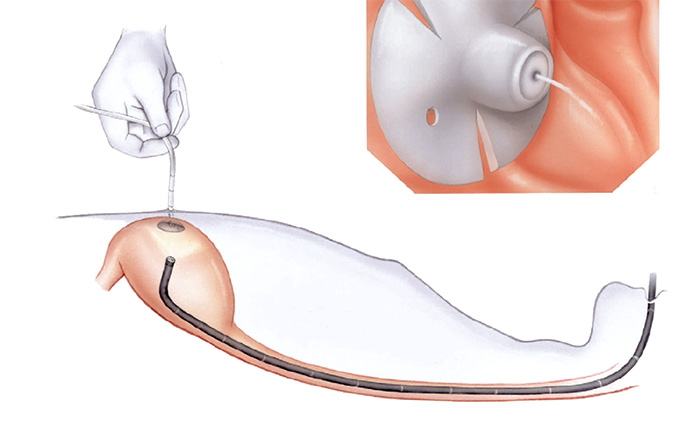

Pacientes que têm o objetivo de emagrecer, podem ter como alternativa a passagem de um balão intragástrico. A passagem do balão é realizada por endoscopia e o procedimento dura cerca de 20 a 30 minutos.

Passagem de Balão Intragástrico

1. O balão intragástrico é introduzido desinsuflado durante a endoscopia e colocado no estômago.

2. Um líquido azul (azul de metileno diluído em soro fisiológico) é colocado dentro do balão através de uma válvula. O volume varia entre 500-700 ml.

3. O aparelho de endoscopia é removido e o balão intragástrico pode ser deixado por um período de até 6 meses.

Pacientes que têm o objetivo de emagrecer, podem ter como alternativa a passagem de um balão intragástrico. A passagem do balão é realizada por endoscopia e o procedimento dura cerca de 20 a 30 minutos.

Passagem de Balão Intragástrico

1. O balão intragástrico é introduzido desinsuflado durante a endoscopia e colocado no estômago.

2. Um líquido azul (azul de metileno diluído em soro fisiológico) é colocado dentro do balão através de uma válvula. O volume varia entre 500-700 ml.

3. O aparelho de endoscopia é removido e o balão intragástrico pode ser deixado por um período de até 6 meses.